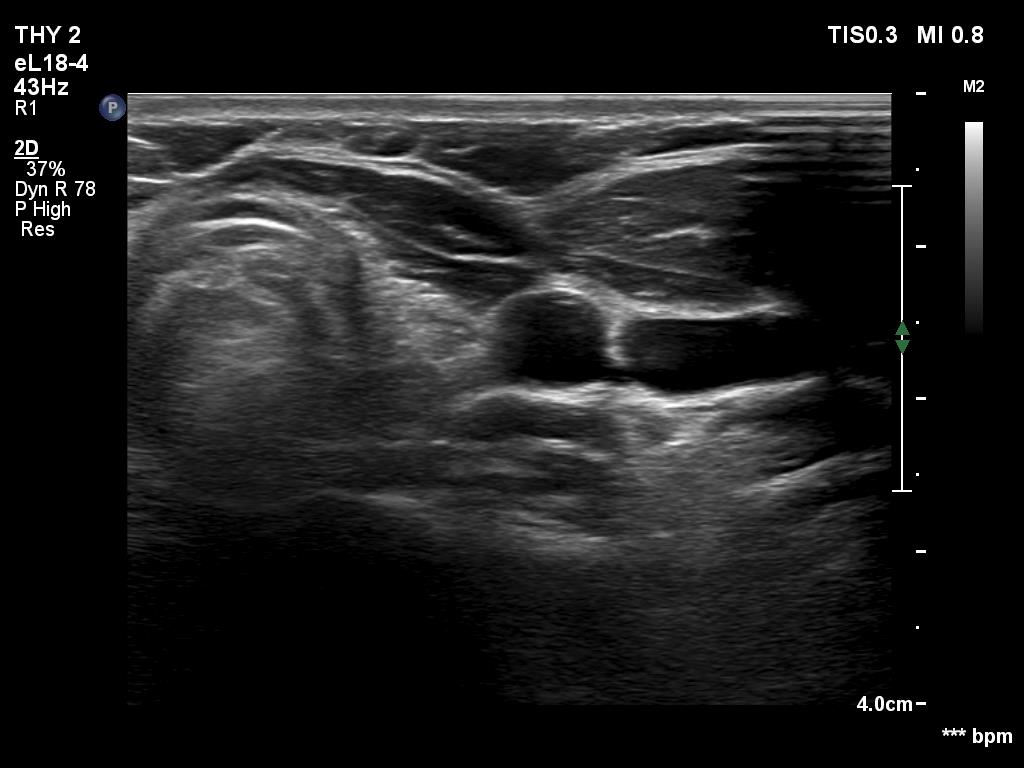

The operated thyroid - case conp 090

18 months after surgery (ultrasonographic picture 2)

Left lobe, transverse scan. The thyroid bed is replaced by connective tissue.